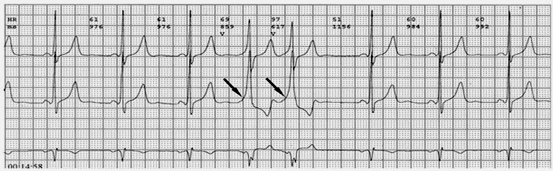

2.心電圖表現(xiàn):典型預激表現(xiàn)為竇性搏動的PR間期<0.12秒,某些導聯(lián)的QRS波時限>0.12秒,QRS波起始部粗鈍(稱delta波),ST段有繼發(fā)改變,T波與主波相反。